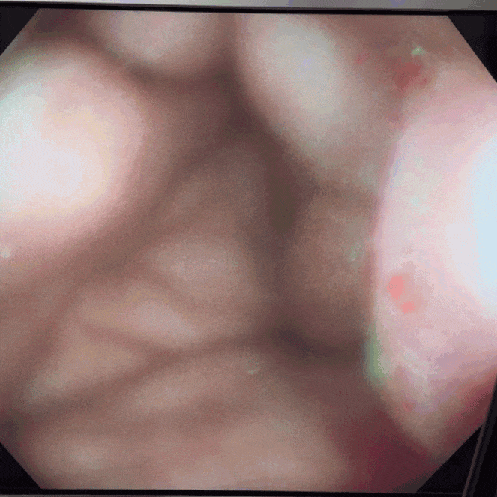

在使用胃镜或肠镜时,送气总是伴随着水流出,导致镜头无法吹干,影响图像观察。

通常是因为水气按钮上的黑色胶圈出现了问题。

上图红圈位置

以上损坏会导致胶圈密封不严,无法阻挡少量水的通过,从而影响您的操作。